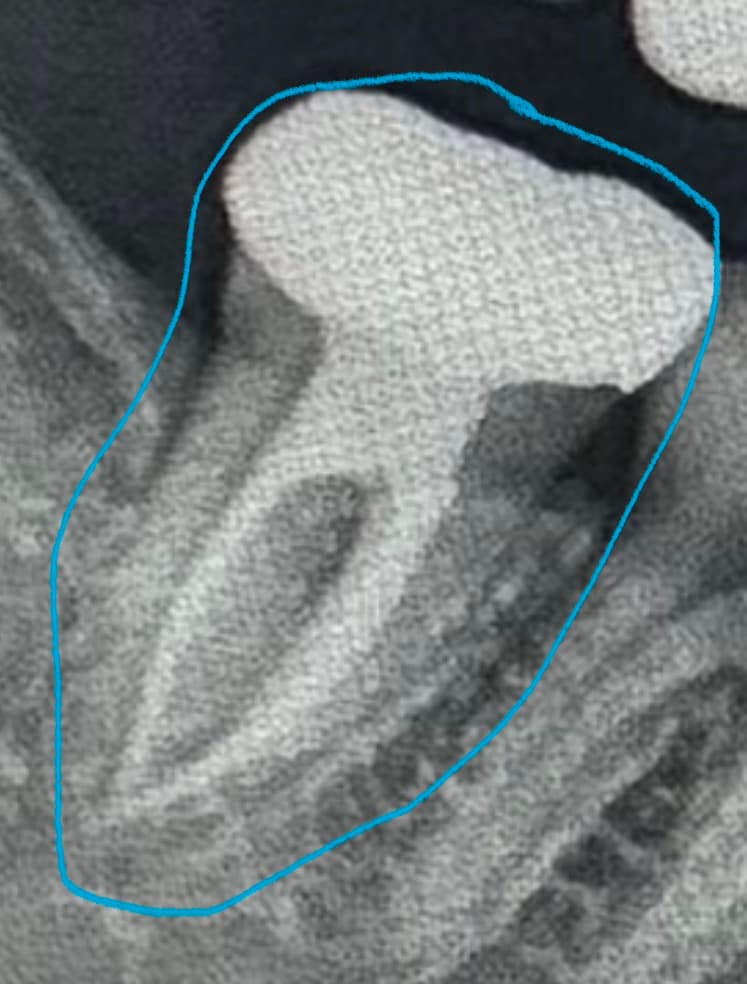

오늘 치과를 방문했는데 오늘 아침부턴 또 통증이 없었어요 며칠전에는 아팠는데 지금은 안아프다고 일단 검사 받으러왔다 말씀드리니 엑스레이 찍고 봐주셨는데 신경치료도 매우 잘되어있고, 염증도없고 치석없이 이가 전부 관리 잘되어있다고 하셔서 스켈링만 받고 나왔는데

신경치료는 잘된 치아 같습니다. 아마 잇몸에 염증이 생겨서 그럴수도 있으니 치과에 가셔서 잇몸치료를 받아보세요.

놓친 신경관이 있어서 그럴 수도 있고요 c형 형태의 고난이도 근관이기에 놓친 숨은 신경관이 있을 수도 있습니다 아니면 치아에 금이가서 그럴 수도 있습니다